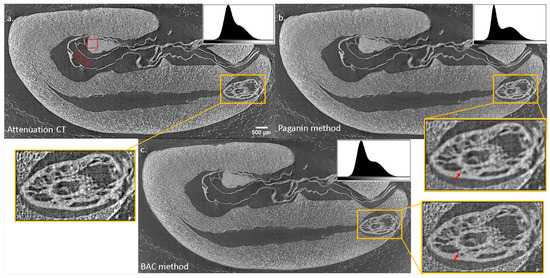

3.1. Example for the Paganin Method

3.2. Example BAC Method